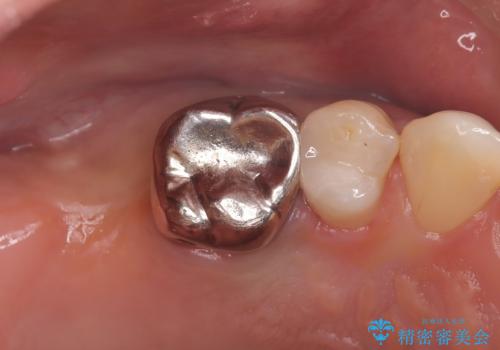

- 治療計画

- 患者様は、右側の奥歯でしっかり噛めないことを主訴に来院されました。診察の結果、右上6・右下6の根管治療が不十分で、感染のリスクがある状態と判断。これらの歯は再根管治療を行い、セラミッククラウンで補綴することにしました。また、右上7・右下7は欠損しており、噛み合わせを回復するためにインプラント治療を計画しました。

まず、右上6・右下6の根管治療を再度行い、根の状態をしっかり整えた上で、セラミッククラウンを装着しました。さらに、欠損していた右上7・右下7にはインプラントを埋入し、セラミッククラウンを装着。治療後は、「奥歯でしっかり噛めるようになり、不安なく食事ができるようになった」と患者様にも大変ご満足いただきました。